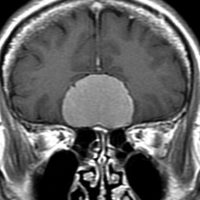

上矢状洞髄膜腫 superior sagittal sinus meningioma

また別な例です。1986年13歳の時に2度の開頭手術を受けましたが,全摘出できずにそのまま経過観察されました。

左の画像は1997年の術前のものです。これを2回に分けて全摘出しました。上矢状洞はやはり冠状縫合のあたりから静脈洞交会まで摘出しました。その下の大脳鎌も全て摘出したので,直静脈洞の上壁を開けることになり,直静脈洞からの激しい出血があり縫合して直静脈洞形成をするのが大変でした。手術後16年が経過しますが再発していませんし,社会人として普通に暮らせています。

この例が教えてくれることは,上矢状静脈洞は全長にわたり切除してしまっても,神経脱落症状を出さないで普通に生きて行かれるということです。